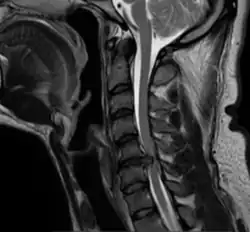

Nach Inzision des vorderen Längsbandes wird die geschädigte Bandscheibe entfernt. Um ggf. einen in den Wirbelkanal verlagerten Bandscheibenvorfall (s. Bild) erreichen und entfernen zu können, wird auch das hintere Längsband abgetragen. Sollten sich auch knöcherne Randsporne (Osteophyten) gebildet haben, die in den Wirbelkanal vorspringen, werden auch diese mit Mikroinstrumenten beseitigt oder einer Miniaturfräse abgeschliffen. Das gilt insbesondere auch für den Nervenkanal (Foramen intervertebrale) auf beiden Seiten, damit die dort austretenden Nerven sicher entlastet sind.

Nachdem so das Implantatlager vorbereitet ist, wird unter leichter Spreizung des Zwischenwirbelraums die Bandscheibenprothese eingesetzt. Dies geschieht unter Kontrolle mit dem Röntgenbildwandler, um eine optimale präzise Platzierung zu erreichen (s. Bild). Sitzt die Prothese fest, wird unter dem Röntgenbildwandler eine kurze Bewegungsprobe gemacht, um sicherzustellen, dass sie auch korrekt funktioniert. Ist dies der Fall, wird die Wunde verschlossen.